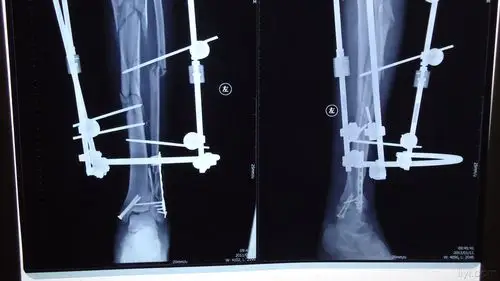

胫骨下段粉碎性骨折组合外固定架治疗1例

胫骨多段骨折外固定架固定

一例胫腓骨远端开放性骨折治疗